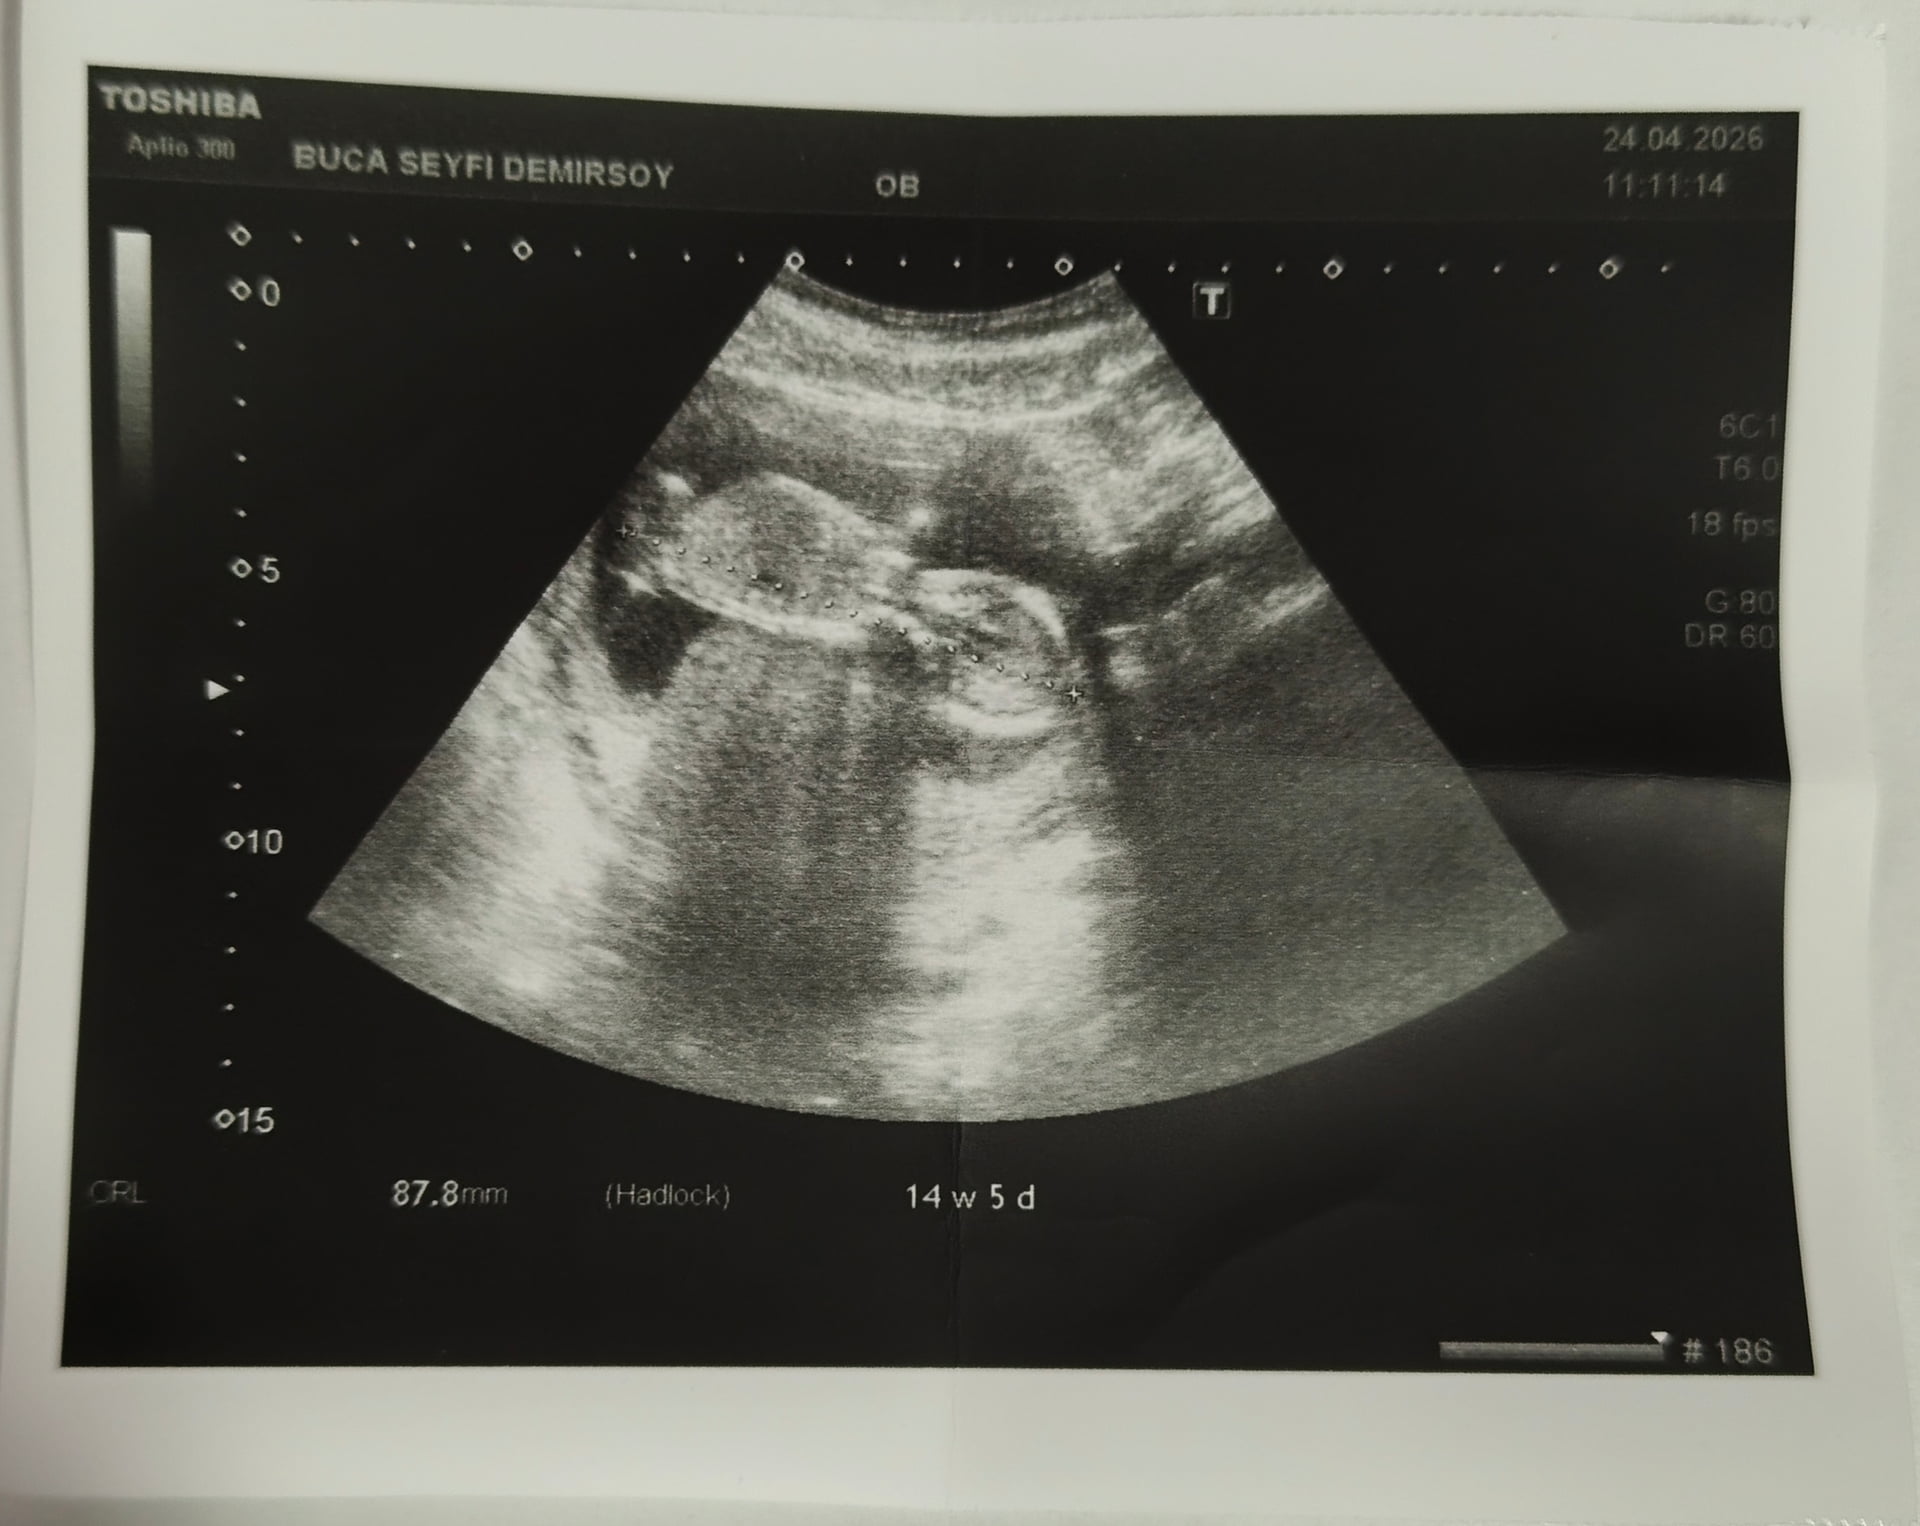

Bence kız

Kızz yüksek oranla %80 felan

Kız benceee

Prenses gibi canım bacak arasından bir çıkıntı yok